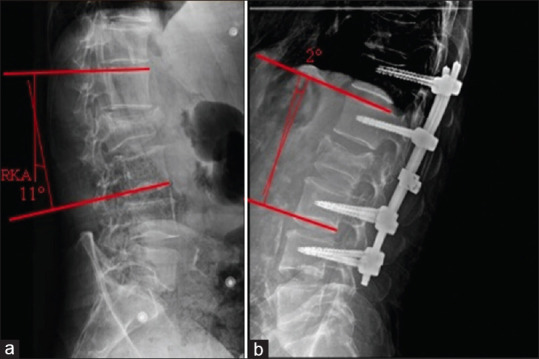

Results: One hundred and four patients were selected; there were 73 males and 31 females with a mean age of 40.94 years. Most of the patients had no significant medical history and were directly transferred from emergency department. Poly trauma was observed in nearly half of the patients. The most common mechanism of injury was fall from height and secondly road traffic accident. At admission, 70% of patients were classified American Spinal Injury Association (ASIA) E, 12.5% ASIA A, and 17.5% had incomplete neurological deficit. Radiological investigations showed that most fractures are located in the thoracolumbar junction (53.85%) followed by lumbar location (36.55%) and thoracic region (9.6%). Most fractures are classified type A (AO classification) with predominance of subtype A3 and A4, frequently located in the thoracolumbar and lumbar region. All patients were operated through posterior approach with pedicle screw fixation and only 36% had in addition posterior decompression. The mean postoperative hospital stay was 5.4 days. The rate of postoperative complications was 2.9%. At the last follow-up, improvement of incomplete neurological deficit was seen in 80% of cases, and a statistically significant correction of the regional kyphosis angle was observed at the thoracolumbar junction.

Conclusion: The posterior approach with pedicle screw fixation is an effective technique for the treatment of thoracolumbar fracture, leading to a good clinical recovery and radiological satisfactory alignment in most of cases with low rate of complications.